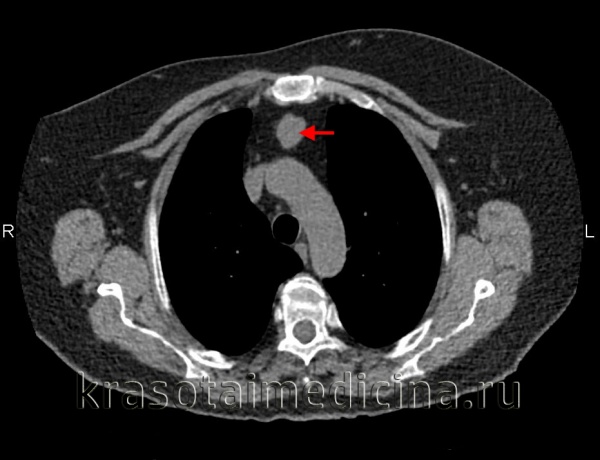

а) Первичные саркомы сердца. Первичные саркомы сердца - наиболее часто встречающиеся (95%) первичные злокачественные опухоли сердца. Они происходят из мезенхимных клеток. Обследуя больных в связи с подозрением на первичную саркому сердца, всегда необходимо также исключить метастазы экстракардиальной опухоли, исходящей из костей скелета или ретроперитонеума. Метастазы саркомы в сердце наблюдаются в 60 раз чаще, чем первичные саркомы сердца. Из клинических проявлений следует отметить затруднение дыхания, боль в груди, симптомы тампонады сердца, реже наблюдаются эмболии, обмороки или внезапная сердечная смерть. Саркому сердца в 75% случаев удается диагностировать с помощью двумерной ЭхоКГ.

Диагностике помогает наличие одновременно выпота в полости перикарда. Для установления диагноза можно выполнить также КТ или МРТ. Роль чреспищеводной ЭхоКГ особенно значительна при локализации опухоли в предсердии. Дифференциальная диагностика с миксомой предсердия упрощается в случае, когда опухоль инфильтрирует стенку желудочка. Присутствие очагов обызвествления наблюдается как в саркомах, так и в миксомах, поэтому данный признак не используется для проведения дифференциальной диагностики.

1. Ангиосаркомы. Ангиосаркомы - наиболее часто встречающиеся саркомы сердца у взрослых. Они локализуются преимущественно в правом предсердии. Часто в опухолевый процесс вовлекается перикард, но нередки также случаи, когда опухолевая инфильтрация распространяется на полые вены и на трехстворчатый клапан. Средний возраст больных с саркомой сердца составляет 40 лет. У мужчин ангиосаркомы встречаются чаще, чем у женщин. Прогноз жизни при ангиосаркоме весьма неблагоприятный. После установления диагноза продолжительность жизни больных составляет лишь 3-4 мес., и изменить прогноз удается лишь путем ранней диагностики ангиосаркомы и радикального ее иссечения.